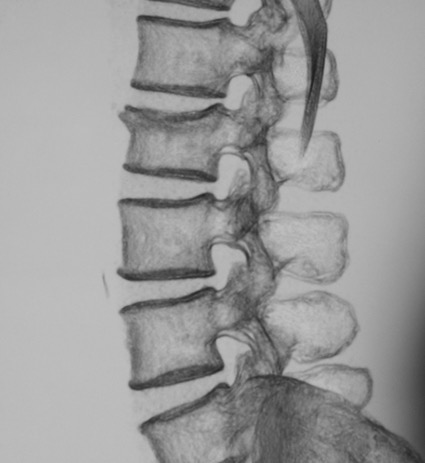

Позвоночный столб является уникальным по своему строению и функциям анатомическим образованием. Во многом благодаря особенностям строения позвоночника человек разительно отличается от всех остальных созданий природы. Ввиду сказанного нельзя не отметить, что ежедневно на человеческий организм, и позвоночник в частности, действуют самые разнообразные нагрузки и силы, сопровождающие нас в повседневной деятельности. Данные факторы приводят к развитию неповторимых в других сегментах организма патологий позвоночника (позвоночного столба), которые обретают самые разнообразные формы течения и клинических проявлений от бессимптомного течения до развития стойкого болевого синдрома. Позднее обращение к врачам-специалистам, изначально неверная диагностика и несвоевременно начатое правильное лечение зачастую приводят неблагоприятным для пациента последствиям:

Пример компрессионного перелома тела второго поясничного позвонка у пожилой пациентки с остеопорозом после низкоэнергетической травмы (поскользнулась и упала на улице)